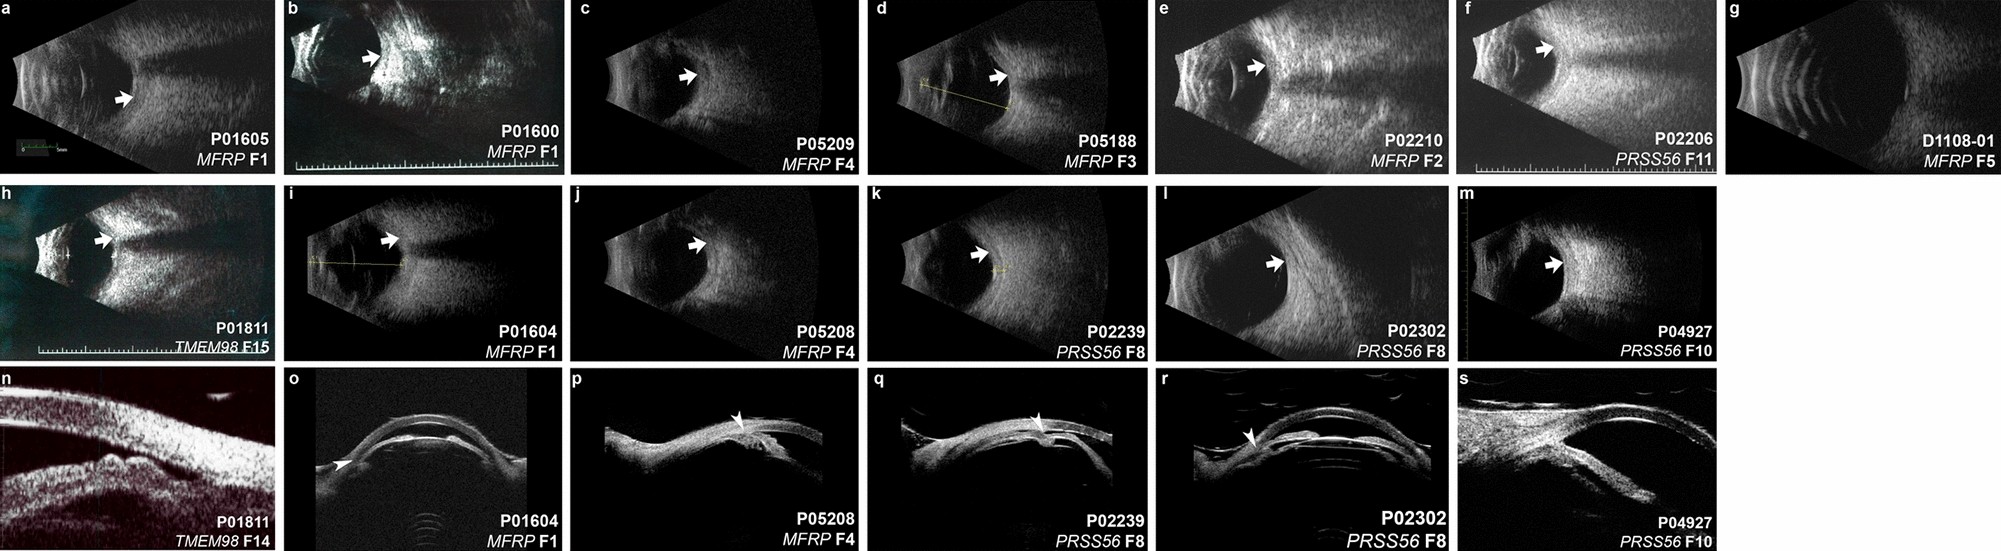

Figure 6

Ultrasonographic features of solved nanophthalmos/high hyperopia families. (a–m) B-scan ultrasound of solved families. There is variability in eye size within and among families, with consistent features of increased sclerochoroidal thickness (arrows). (n–r) Ultrasound biomicroscopy (UBM) of solved families. Plateau iris (n), and angle closure (o–r, arrowheads) are consistent features among families. There are no clear distinctions on B-scan or UBM among different genetic causes.